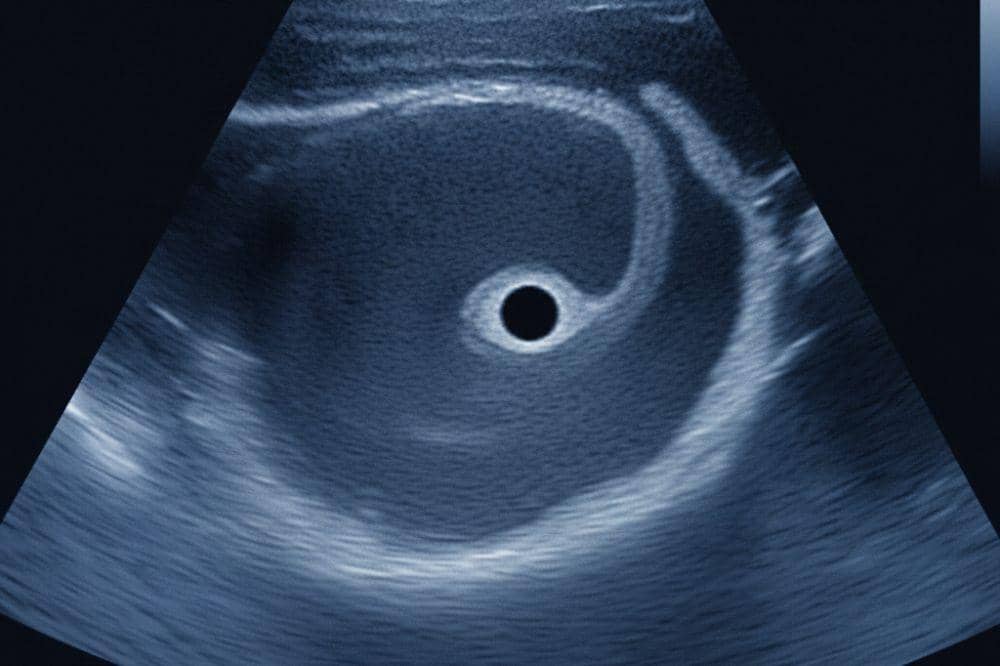

2. Kantung kehamilan dapat terlihat dengan USG

Kantung kehamilan bisa dideteksi dengan pemeriksaan ultrasonografi (USG), terutama melalui ultrasonografi transvaginal. Namun, jika USG dilakukan terlalu dini, kantung kehamilan mungkin belum terlihat.

Kantung kehamilan biasanya mulai terlihat melalui pemeriksaan USG saat usia kehamilan mencapai sekitar 3–5 minggu. Pada tahap paling awal ini, yang tampak pertama kali di layar USG adalah kantung kehamilan itu sendiri, sementara janin belum terlihat.

Selanjutnya, akan muncul yolk sac dalam kantung kehamilan, yang berfungsi memberi nutrisi sementara bagi embrio sebelum plasenta mulai bekerja. Pada beberapa kasus, kantung kuning baru terlihat jelas pada usia 5–6 minggu, menandai bahwa kehamilan berkembang.

Seiring perkembangan, embrio mulai tampak di dalam kantung kehamilan. Pada usia 6 minggu, pola janin awal terlihat. Memasuki usia 7–8 minggu, mulai menunjukkan struktur yang lebih jelas.